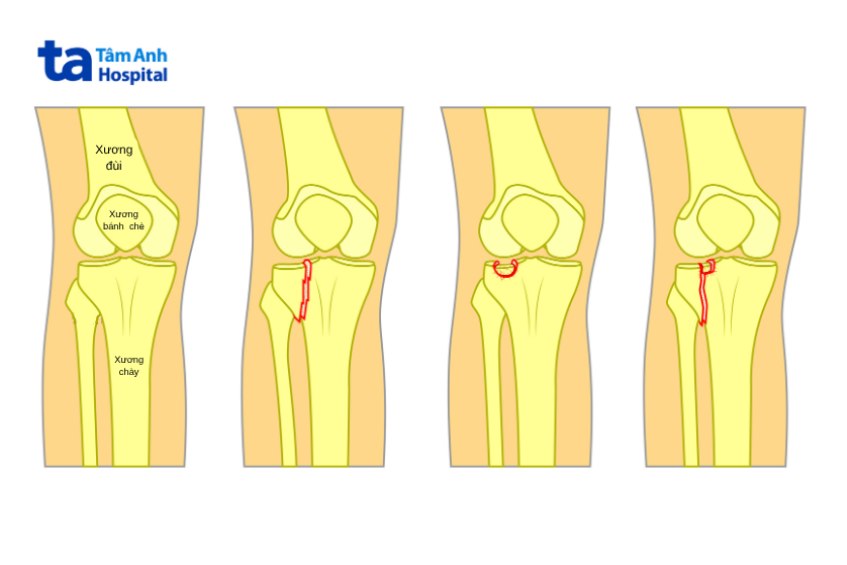

Vỡ mâm chày được phân loại theo nhiều cách thức khác nhau. Tuy nhiên, Schatzker được xem là cách phân loại phổ biến nhất, cụ thể: (2)

Gãy tách mâm chày ngoài, mức độ lún hoặc di lệch dưới 4 mm. Đây là phân loại ít nghiêm trọng nhất, thường xuất hiện ở người trẻ, người có hệ thống nội cơ xương khớp khỏe mạnh.

Schatzker II là phân loại bổ biến nhất, được nhận biết thông qua dấu hiệu gãy tách mâm chày ngoài, phần mặt khớp bị lún vào hành xương.

Đặc trưng bởi tình trạng lún trung tâm mâm chày ngoài, trong khi bờ xương còn nguyên vẹn. Không giống các phân loại khác, Schatzker III thường đến từ chấn thương năng lượng thấp ở người bị loãng xương, thoái hóa xương khớp hoặc các vấn đề sức khỏe liên quan.

Được chia thành 2 phân loại chính là gãy tách hoặc gãy lún mâm chày trong, có ảnh hưởng đến mô mềm (da, cơ, thần kinh, dây chằng, mạch máu) xung quanh.

Gãy tách mâm chày hai lồi cầu (trong và ngoài).

Gãy tách mâm chày với xương chày, có thể gây chấn thương đáng kể các mô mềm quanh đầu gối. Đây được coi là mức độ nặng nhất của vỡ mâm chày.